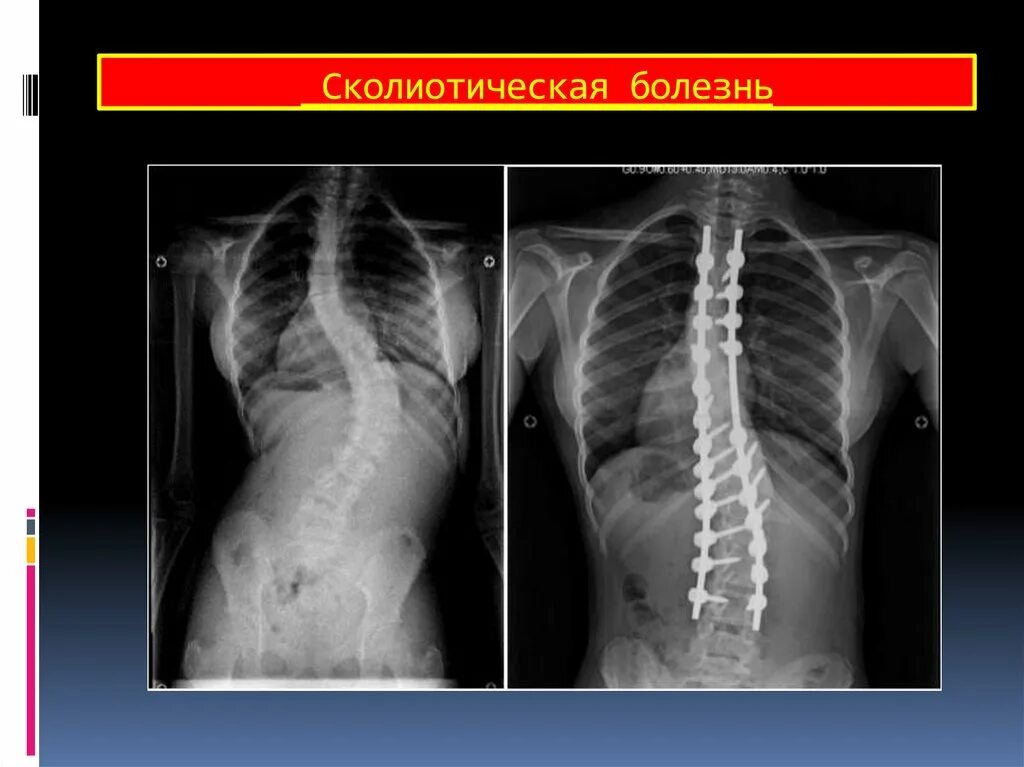

Деформация позвоночных